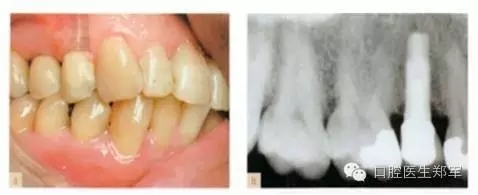

單顆牙缺失的種植體修復:與自然牙齒修復相似,都是由咬合原則指導。種植體中心咬合接觸,咬合面減徑(如果可能的話),牙尖平坦(如果可能的話),全牙列在最大牙尖交錯時能夠同時接觸,以上這些都具備臨床和生物力學意義。修復體不應該有非正中干擾,但是適當?shù)臅r候可以設計成部分選擇性非正中引導。(圖1和圖2)

圖1 a-b 單顆前磨牙種植、良好的接觸、同時全口咬合接觸、以種植體中心為咬合接觸點。 |